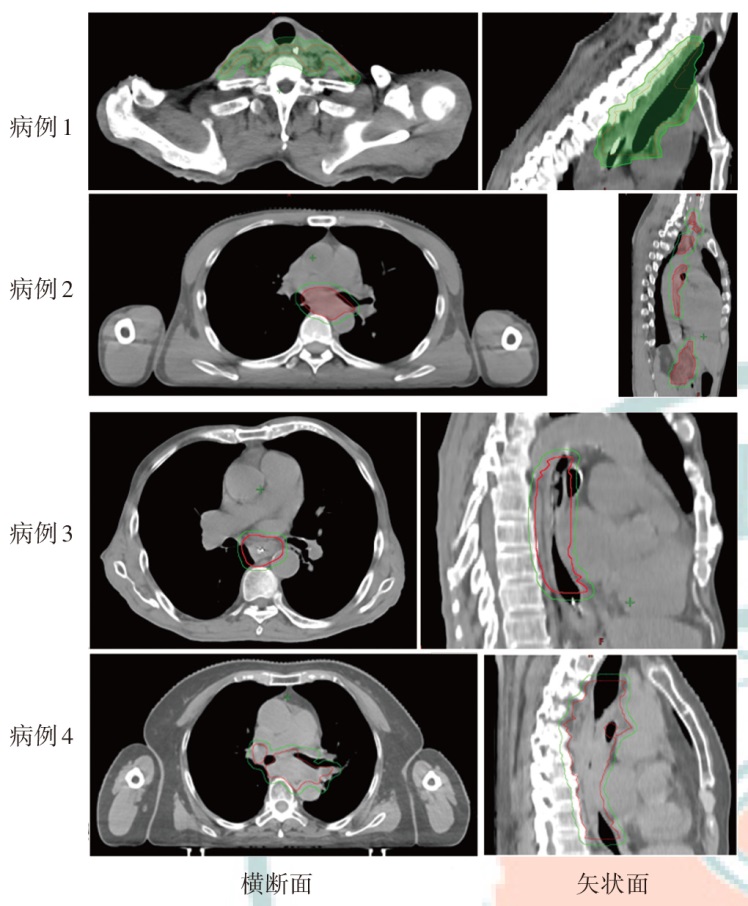

目的探讨食管癌质子放疗计划与光子放疗计划的剂量学特点。方法以山东省肿瘤防治研究院(山东省肿瘤医院)2024年1月至2024年4月收治的需行放疗的4例食管癌患者为研究对象,靶区分别为颈段、胸中段及全段食管,以及涉及的淋巴引流区。根据临床靶区和危及器官限值的要求,分别设计质子调强放疗(IMPT)和光子固定野调强放疗(IMRT)两种放疗计划。比较两种计划的靶区适形指数(CI)、均匀性指数(HI)、梯度指数(GI)以及危及器官的剂量学差异,通过评估体内10%、30%和50%的剂量体积比较患者体内额外的剂量沉积。结果4例患者IMPT计划的HI(0.12、0.10、0.06和0.08)、GI(3.11、3.21、2.43和2.72)、CI(0.59、0.60、0.77和0.72)均小于IMRT计划(HI分别为0.15、0.13、0.10和0.11,GI分别为4.52、5.14、3.09和3.92,CI分别为0.81、0.77、0.91和0.85)。与IMRT计划相比,4例患者IMPT计划的全肺受量指标中,V5分别下降34.1%、55.0%、79.7%和60.3%;V20分别下降48.3%、43.9%、65.8%和40.8%,Dmean分别下降43.4%、57.2%、76.2%和45.4%;心脏V30分别下降36.2%、45.3%、40.1%和52.4%,Dmean分别下降96.6%、57.9%、58.5%和55.3%。对于胸中下段靶区,肝脏在IMPT计划中得到明显保护(Dmean较IMRT计划下降76.0%)。患者体内额外剂量沉积方面,IMPT计划中10%剂量体积减少了45.0%~61.4%;30%剂量体积减少了41.2%~61.8%;50%剂量体积减少了34.8%~61.6%。结论通过比较4例食管癌的IMPT和IMRT计划相关剂量学参数,IMPT计划在降低肺组织、心脏以及肝脏器官的剂量方面具有优势,并能够减少患者体内额外剂量沉积。

ObjectiveTo explore the dosimetric characteristics of proton radiotherapy plan and photon radiotherapy plan for esophageal cancer.MethodsFour patients who were admitted to Shandong Cancer Hospital and Institute from January 2024 to April 2024 with esophageal cancer (cervical, middle thoracic and total esophageal tube, as well as the lymphatic drainage areas involved) and required radiotherapy were selected as the research subjects. Intensity modulated proton therapy (IMPT) and intensity modulated radiation therapy (IMRT) plans were designed respectively based on the clinical target volume and the dose constraints for organs at risk (OARs). Dosimetric parameters, including conformity index (CI), homogeneity index (HI), gradient index (GI) for target coverage, as well as OARs dosimetric parameters were evaluated. The volume of additional dose deposition in the body was compared by assessing regions receiving 10%, 30%, and 50% of the prescription dose.ResultsFor all four cases, IMPT plans yielded lower HI values (0.12, 0.10, 0.06, and 0.08) than IMRT plans (0.15, 0.13, 0.10, and 0.11), and the GI values of IMPT plans (3.11, 3.21, 2.43, and 2.72) was lower than IMRT plans (4.52, 5.14, 3.09, and 3.92). Moreover, the CI of the IMPT plans (0.59, 0.60, 0.77, and 0.72) was inferior to IMRT plans (0.81, 0.77, 0.91, and 0.85). Compared with the IMRT plans, in the whole lung dose indicators of the IMPT plans for the 4 patients, V5decreased by 34.1%, 55.0%, 79.7% and 60.3%, respectively; V20decreased by 48.3%, 43.9%, 65.8% and 40.8%, respectively, and Dmeandecreased by 43.4%, 57.2%, 76.2% and 45.4%, respectively. V30of the heart decreased by 36.2%, 45.3%, 40.1% and 52.4%, respectively, and Dmeanof heart decreased by 96.6%, 57.9%, 58.5% and 55.3%, respectively. For the middle and lower thoracic target area, the liver was significantly protected in the IMPT plan (Dmeandecreased by 76.0% compared with the IMRT plan). In terms of the additional dose deposition in the patient's body, IMPT plans reduced the volumes receiving 10%, 30% and 50% of the prescription dose by 45.0%-61.4%, 41.2%- 61.8% and 34.8%-61.6%, respectively, compared with the IMRT plans.ConclusionsBy comparing the dosimetric parameters of IMPT and IMRT plans for 4 cases of esophageal cancer, the IMPT plans have advantages in reducing the doses to lung tissue, heart, and liver, and can also reduce additional dose deposition in the patient's body.